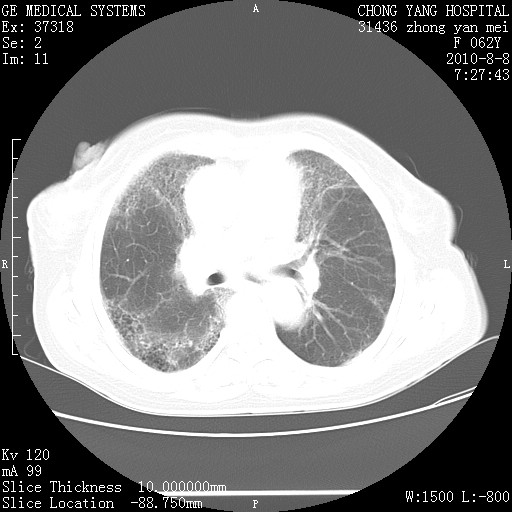

标题: CT28269:F62Y咳嗽胸痛数月。 [打印本页]

标题: CT28269:F62Y咳嗽胸痛数月。

两肺弥漫性间质纤维化伴继发性支扩。

考虑特发性肺间质纤维化

考虑两肺间质性肺炎并肺间质纤维化。

双肺间质纤维化合并感染、肺气肿

双肺间质纤维化

两肺间质纤维化并牵拉性细支气管扩张。

考虑两肺间质性肺炎并肺间质纤维化,肺气囊形成。

两肺间质改变,纵隔淋巴结肿大,需要考虑结节病的可能。